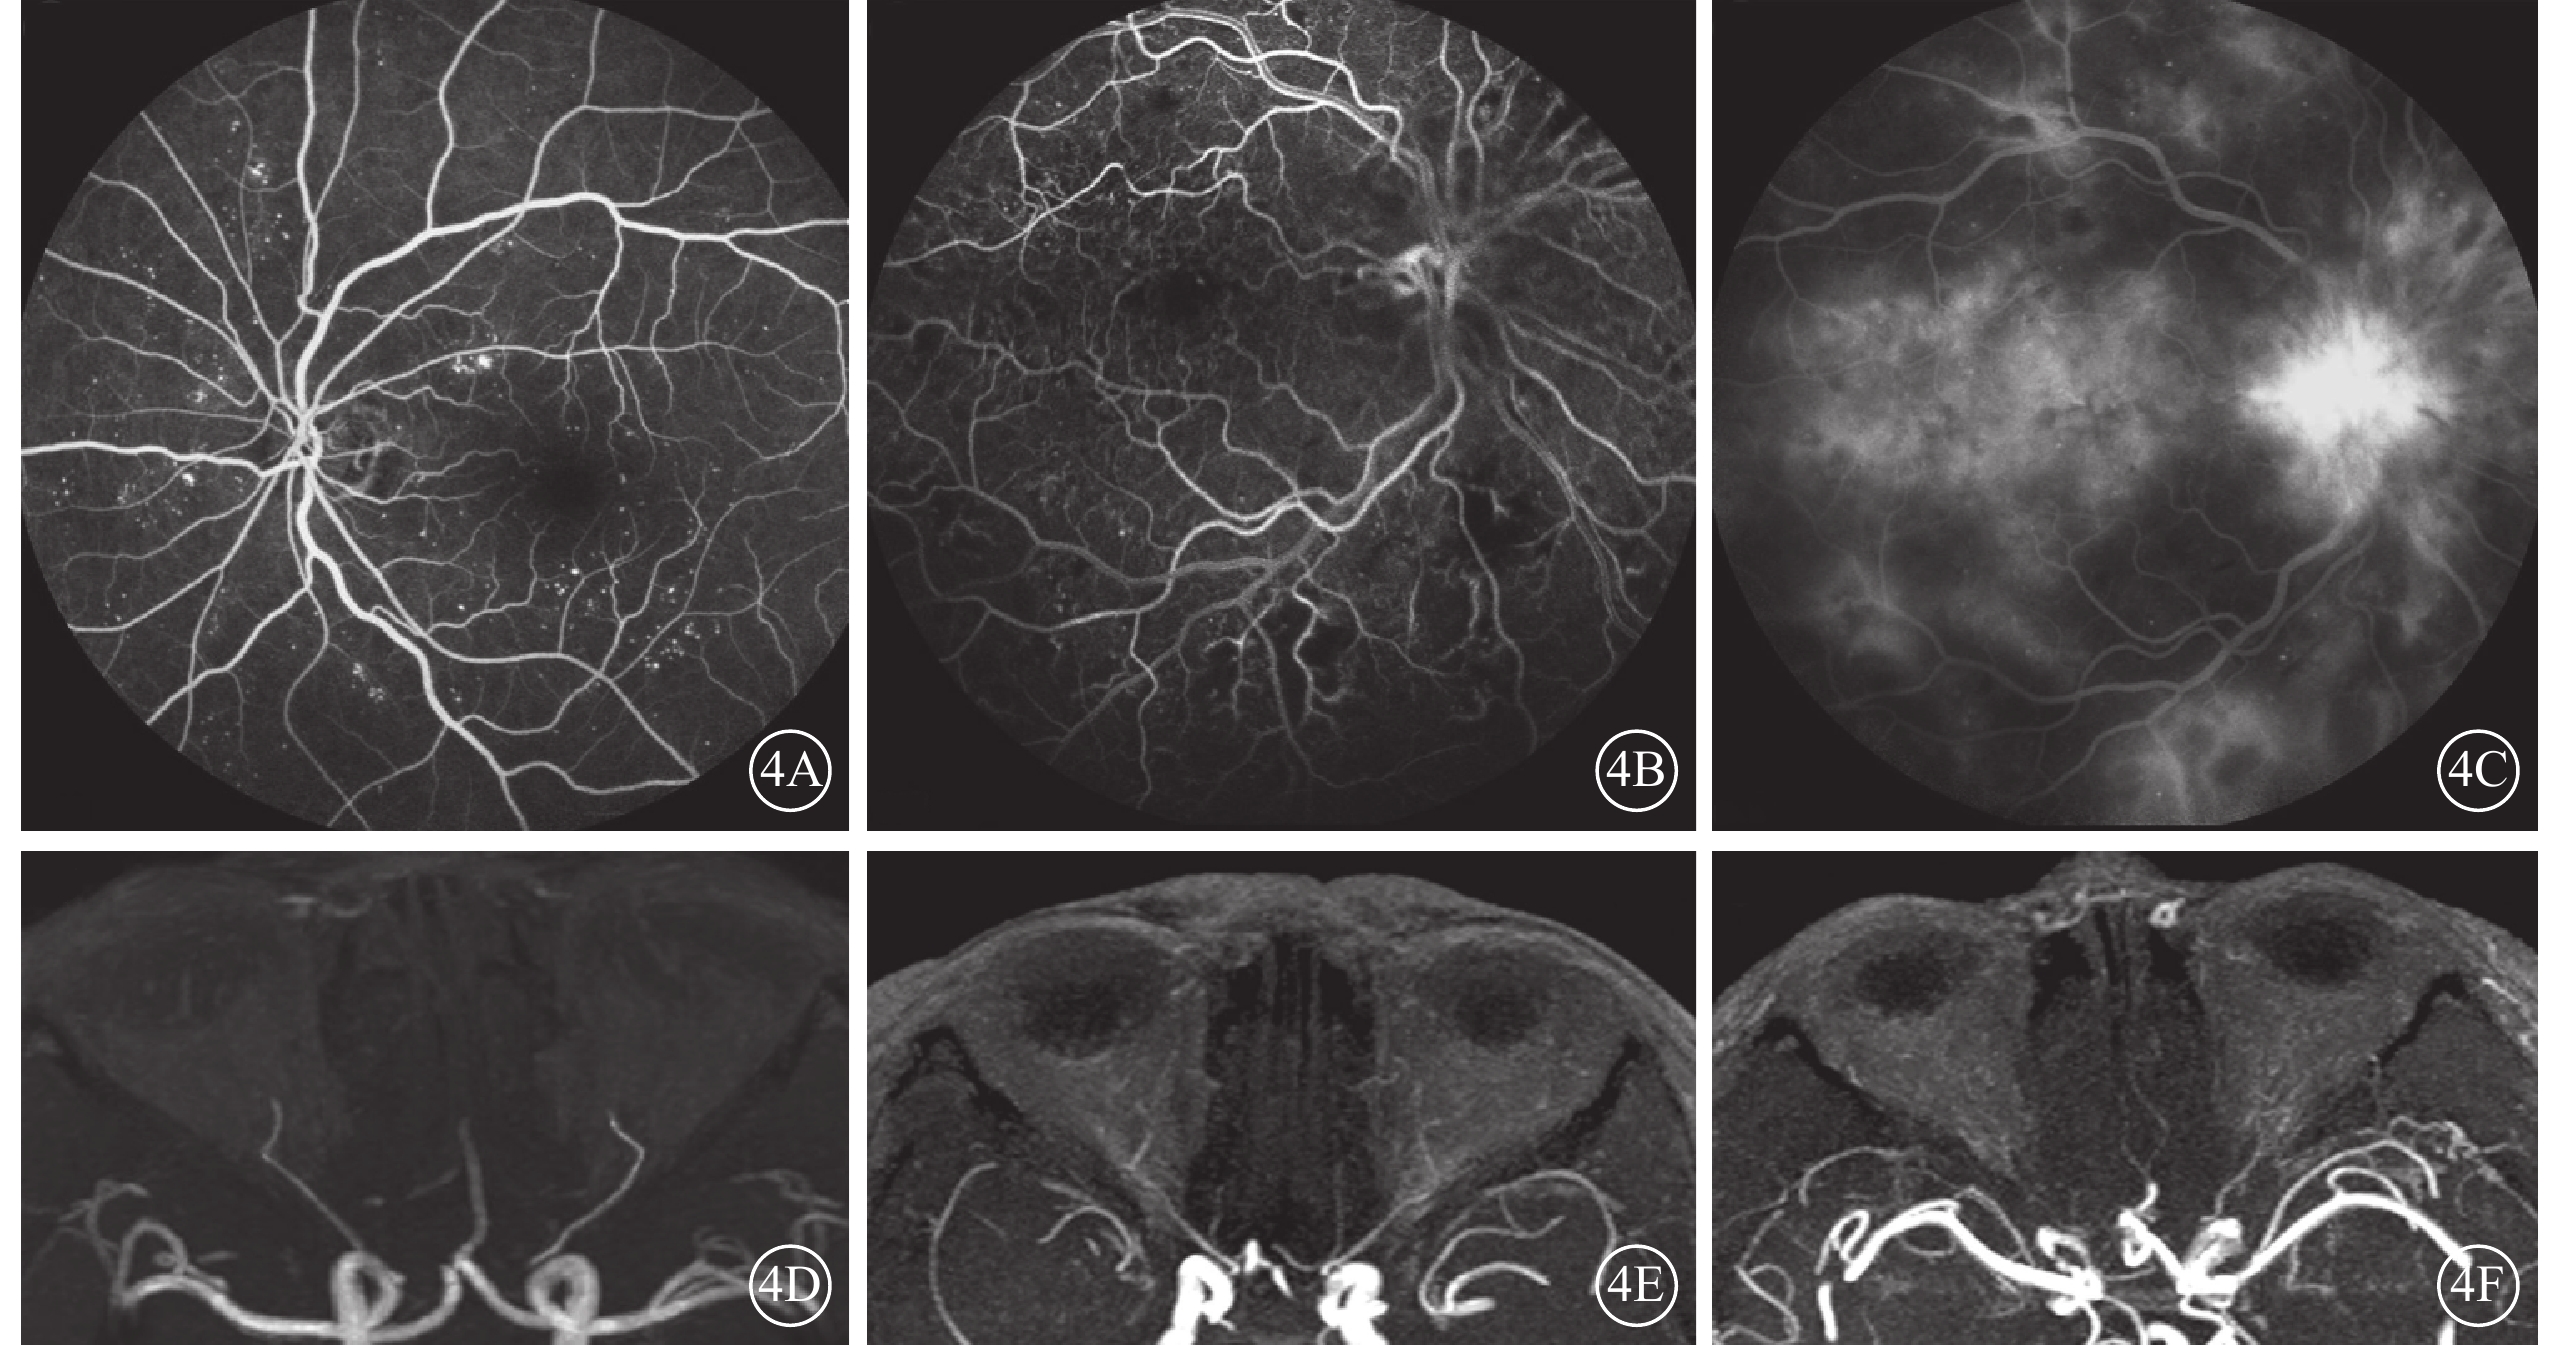

DR組72只眼中,FFA無明顯病變期、背景期、增生前期、增生期分別為8、12、22、30只眼。 相關性分析結果顯示,DR組眼動脈MRA分級與FFA分期呈顯著相關性(r=0.405,P=0.000);分級比較顯示DR組FFA分期越重,眼動脈MRA顯影越差(表2,圖4)。

圖4

DR患者FFA、MRA像。4A~4C. FFA像,分別為背景期、增生前期、增生期;4D~4F. 4A~4C同側眼動脈MRA像,分別為0級、Ⅰ級、Ⅱ級。FFA分期越重,眼動脈MRA顯影越差

圖4

DR患者FFA、MRA像。4A~4C. FFA像,分別為背景期、增生前期、增生期;4D~4F. 4A~4C同側眼動脈MRA像,分別為0級、Ⅰ級、Ⅱ級。FFA分期越重,眼動脈MRA顯影越差

DR組72只眼中,FFA無明顯病變期、背景期、增生前期、增生期分別為8、12、22、30只眼。 相關性分析結果顯示,DR組眼動脈MRA分級與FFA分期呈顯著相關性(r=0.405,P=0.000);分級比較顯示DR組FFA分期越重,眼動脈MRA顯影越差(表2,圖4)。

圖4

DR患者FFA、MRA像。4A~4C. FFA像,分別為背景期、增生前期、增生期;4D~4F. 4A~4C同側眼動脈MRA像,分別為0級、Ⅰ級、Ⅱ級。FFA分期越重,眼動脈MRA顯影越差

圖4

DR患者FFA、MRA像。4A~4C. FFA像,分別為背景期、增生前期、增生期;4D~4F. 4A~4C同側眼動脈MRA像,分別為0級、Ⅰ級、Ⅱ級。FFA分期越重,眼動脈MRA顯影越差